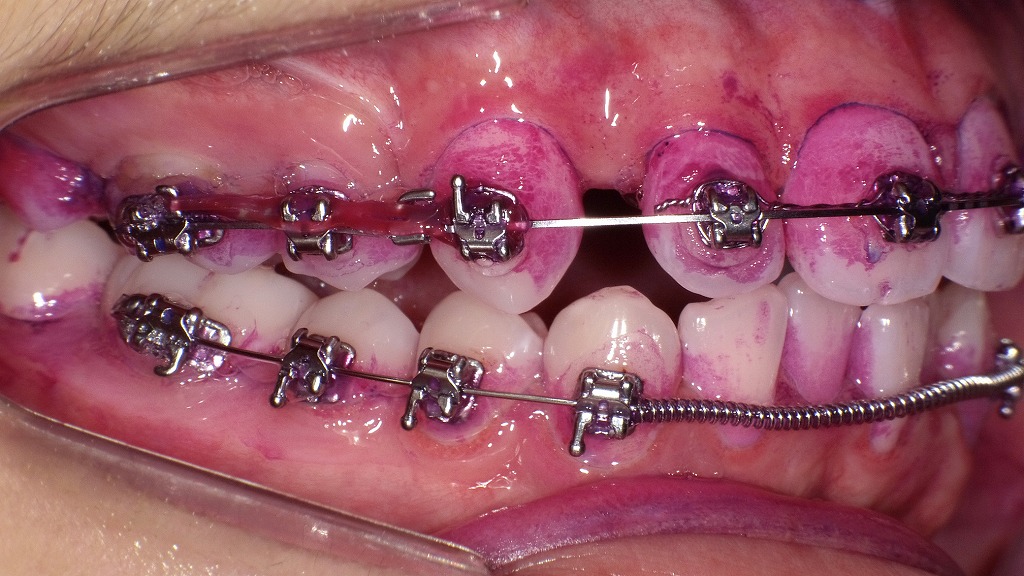

矯正装置がついていると、食べ物がブラケットやワイヤーの隙間に詰まりやすく、虫歯・歯周病のリスクが高まります。そのため、矯正中の口腔ケアは“いつも以上に丁寧に”が基本です。

また、ブラケットやワイヤーの隙間に食べ物が詰まりやすく、虫歯・歯周病のリスクが上がるため、丁寧なブラッシングや補助器具の活用が必要です。